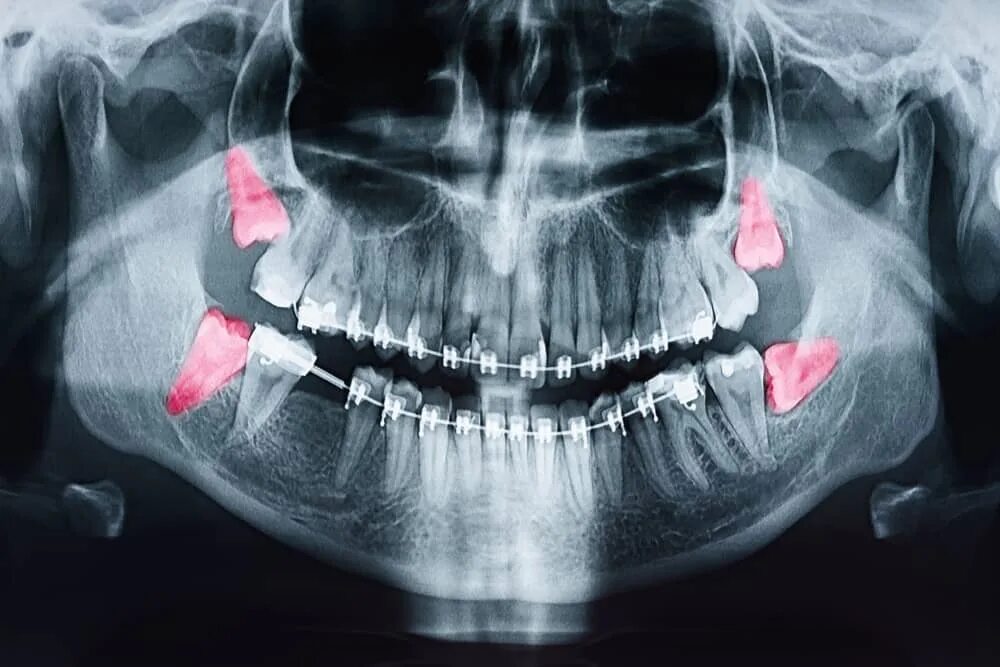

Зубы зажаты